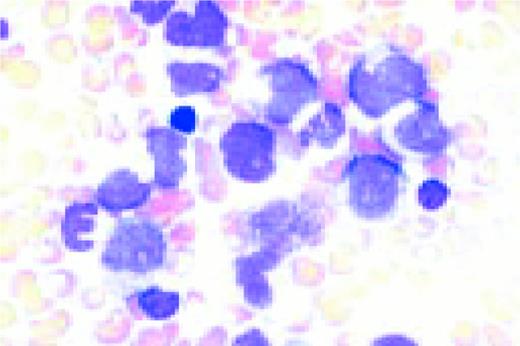

Acute nonlymphoblastic leukemia, FAB classification M5a (L) and M5b (R). The M5a blasts have a moderate amount of cytoplasm and somewhat coarse nuclei. The nucleoli are not unusually prominent. The blasts were positive with the nonspecific esterase stain, and the patient had an associated t(9;11) chromosome abnormality.

The predominant M5b cell is a promonocyte. This cell is characterized by abundant cytoplasm with numerous scattered azurophilic granules and a nucleus with finely dispersed nuclear chromatin. The nuclei are marked by extensive lobulation and creasing. Some of the nuclei have a cerebriform appearance.FIG69